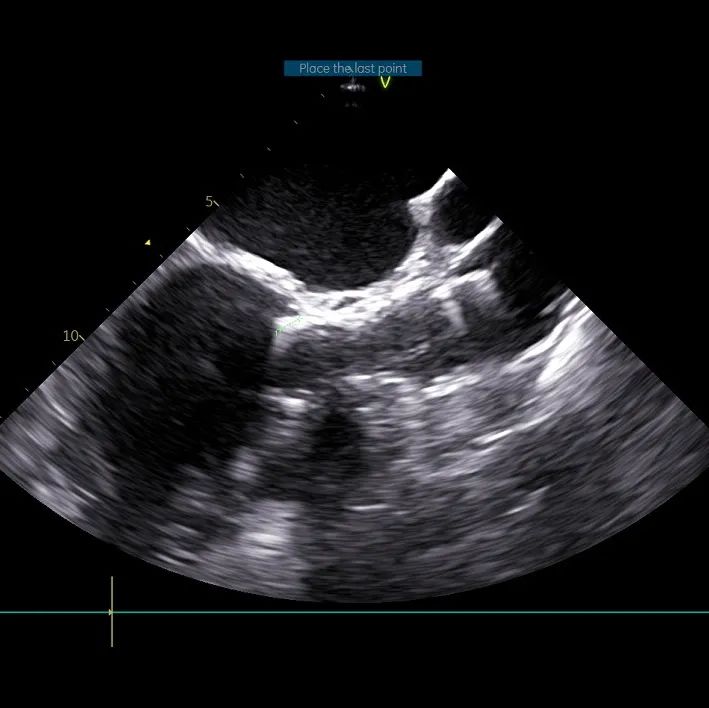

3. 全程无造影剂超声引导下行TAVI手术对超声团队高精度和快速判断要求极高,了解手术过程并同频配合术者手术操作,同时要求术者对超声解读深刻。

术中导丝跨瓣后20mm球囊预扩,超声判断冠脉风险尚可,植入L23 VenusA Plus可回收瓣膜位置良好,用23mm球囊后扩支架下缘,微少量瓣周漏。

术后即刻血压135/65mmHg,狭窄解除,释放后超声测量瓣下支架长度6mm标准位释放瓣膜位置完美。整台手术用时不足1.5小时,麻醉、超声等团队全程协作为手术顺利完成保驾护航。